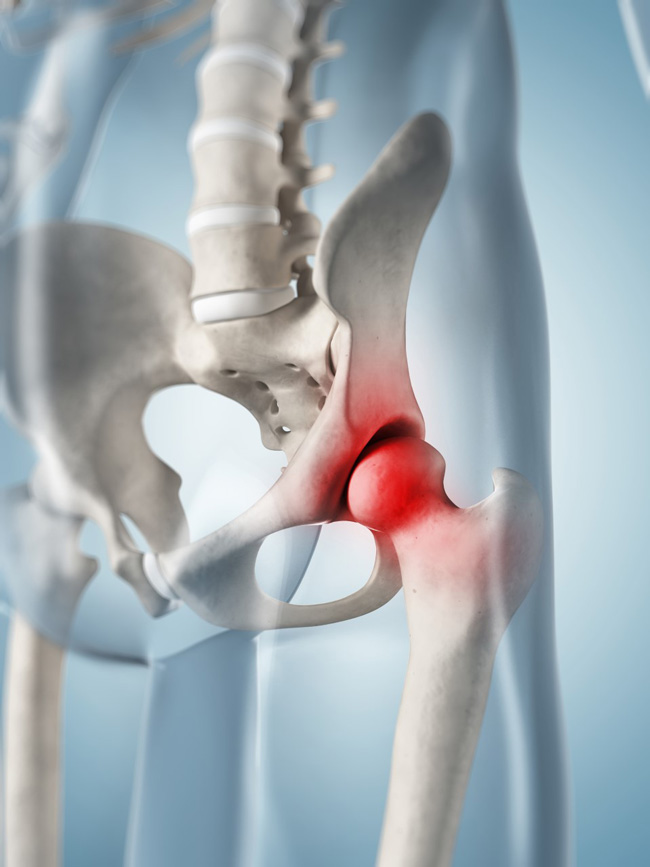

Фотографии и схемы: Коксит правого тазобедренного сустава